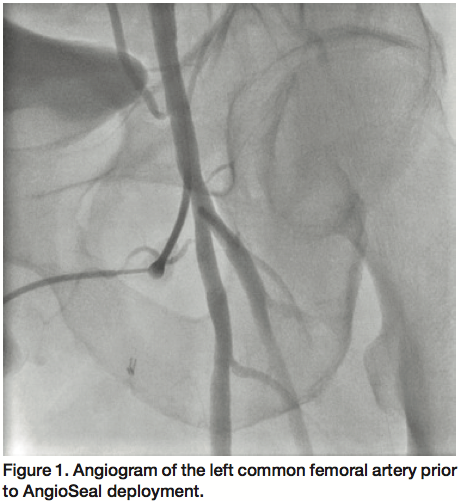

Access was obtained in the right common femoral artery and selective left external iliac artery angiogram was performed, which confirmed hazy thrombotic occlusion of the left common femoral artery at the site of AngioSeal (St. Jude) deployment with reconstitution at the bifurcation of the left superficial femoral and profunda femoris arteries (Figure 2). With the support of a 4 Fr glide catheter, an angled Glidewire (Terumo Medical) was used to cross the occlusion into the distal superficial femoral artery (SFA) with a gradient of 50 mmHg across the occlusion. Rheolytic thrombectomy was then performed using an AngioJet catheter (Medrad Interventional) with multiple runs into the SFA (Figure 3) and profunda femoris artery with improvement in flow across the lesion but persistence of residual thrombus. The glidewire was then exchanged for a Confianza Pro 0.014 mm wire (Asahi Intecc) and laser atherectomy was performed using a 1.7 mm Turbo Elite laser catheter (Spectranetics) utilizing fluence/rate settings of 40/40, 60/60, and 60/80 serially (Figure 4) with further improvement of flow across the left common femoral artery.